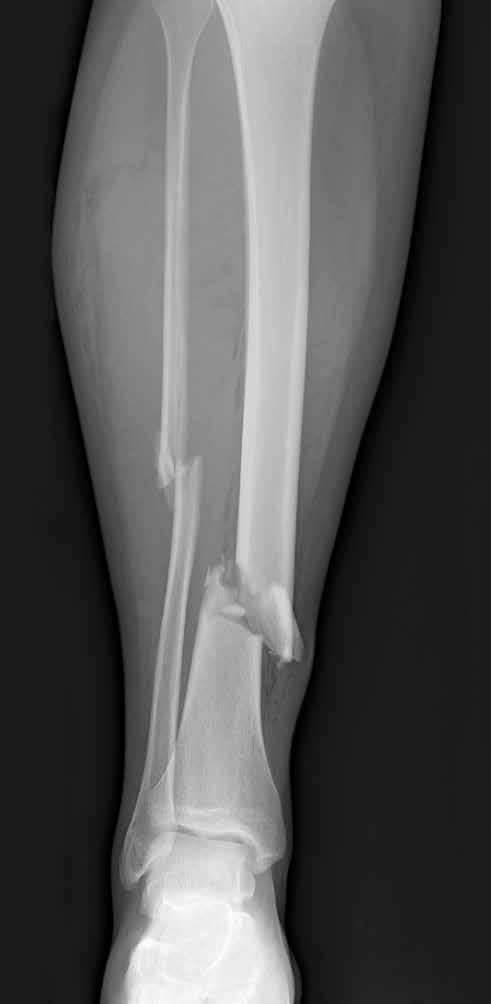

The 1950s: A boy with his leg in traction after a football injury.